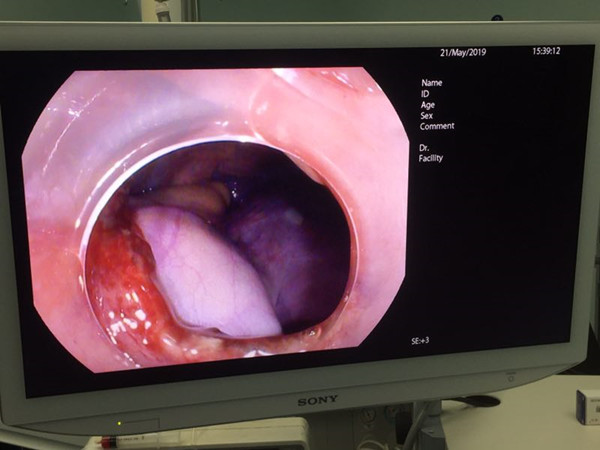

患者为男性18岁青年。间断性胃痛数年,近1年症状渐明显加重。2018年8月超声胃镜发现十二指肠占位,横截面约1.1cm,2019年2月复查内镜,肿物直径约1.5cm。近日门诊复查,肿物直径增大至2.2cm,门诊以“十二指肠肿瘤”收治入院。由于肿物逐渐增大,性质不明确,患者心理负担较重,强烈要求手术切除。但病变位于十二指肠球降移行部小弯侧,向腔内椭圆状突出,单纯外科手术,容易迷失病变,手术路径不畅。单纯消化内镜切除,要全层切开,切口内镜缝合困难较大。经普外科和消化科会诊讨论后,认为双镜联合手术较为稳妥可行。在普外科主任陈熹教授和消化科主任王进海教授的协调指导下,于2019年05月21日实施腹腔镜-胃镜联合手术。在静吸复合全麻下,消化内镜组由邹百仓副主任医师主刀,安苗护师协助配合。腹腔镜组由吴涛副主任医师主刀,杨屹副主任医师及范萌主治医师协助。胃镜下确定肿瘤部位后,粘膜下注射后环切瘤体周围粘膜,暴露瘤体,剥离至肌层,瘤体基底部与浆膜黏连,随行全层切开,完整切除瘤体,创面直径3cm,创面无活动出血,切除时间约30分钟。腹腔镜组随行创面缝合关闭,腹腔镜下探查切口部位及大小后,逐层严密缝合,冲洗腹腔,肝下间隙留置乳胶引流管,查腹腔内无活动性出血,清点器械辅料无误后,缝合关闭刺口,逐层关腹术毕。瘤体标本大小2.0X2.0X1.5cm。术后患者安返病房,手术全程约70分钟。术后患者恢复稳定,3天后进食,6天后出院。

普通光内镜病变图